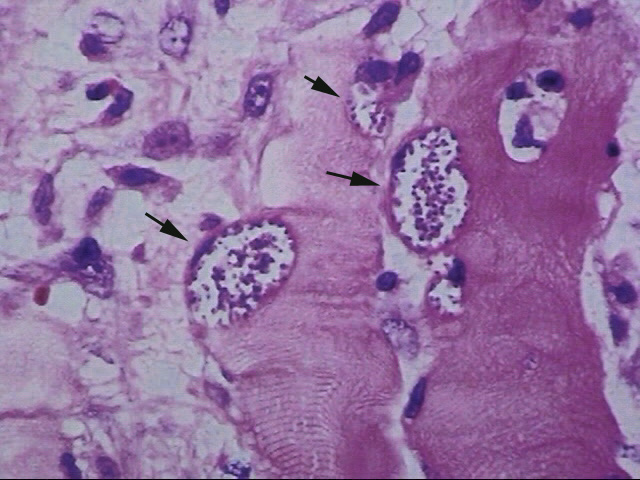

toxoplasmosis-筋肉の病変

右頸部腫瘤の生検組織所見では, 横紋筋内にmicroorganismらしき構造物が認められた。